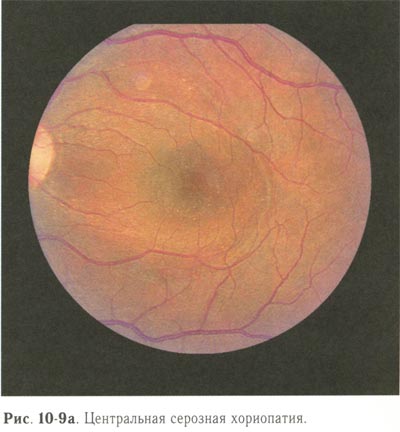

Перед лазерной коагуляцией необходимо провести ФАГД для выявления точки фильтрации и определения её локализации. Применяют 2 вида лазерной коагуляции: при наличии точки фильтрации коагуляты II степени наносятся в месте её локализации под контролем ФАГД, при отсутствии точки фильтрации производится подковообразная лазерная коагуляция по краю отслойки пигментного эпителия (рис. 10-9, 10-10; см. рис. 10-12).

Центральная серозная хориопатия. |